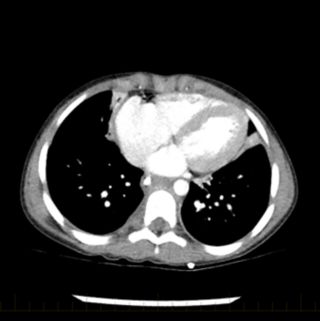

Neuroblastoma is a rare type of cancer that mostly affects babies and young children. Most neuroblastomas develop in the abdomen especially in the adrenal glands. Neuroblastoma is a tumor of nerve tissue that develops in infants and children and can occur in many areas of the body.

Swelling and bruising of the area ar See more. Your childs doctor conducts a physical exam to check out any signs and. Neuroblastoma is the most common pediatric extracranial soft-tissue tumor accounting for approximately 8 of childhood malignancies.

An abdominal mass either felt during an examination or seen as a swollen abdomen 2. The results of 112 children with neuroblastoma treated at the Memorial Sloan-Kettering Cancer Center between 1949 and 1980 were analyzed. Many of these children with neuroblastoma present with spread to other parts of the body such as the bone marrow bone lymph nodes liver and skin.